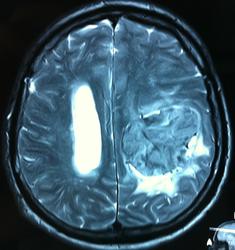

Начало вот здесь http://www.radiomed.ru/cases/kt-gms-obemnoe-obrazovanie-levoi-gemisfery-bolshogo-mozga-vnutrizheludochkovaya-meningioma. Пациент оперирован (меня сначала дезинформировали по поводу операции), перед операцией состояние ухудшилось, возникла правосторонняя гемиплегия, которая осталась и после декомпрессии. МРТ, КТ снимки и выписку предоставила супруга пациента, снимал на iphone, простите за качество, дисков с исследованиями не записывали. Надеюсь вопрос по данному случаю исчерпан.

Т2

И Вы считаете, что эта опухоль имеет интравентрикулярную локализацию?

Изначально по КТ я так предпологал, а теперь на 100% уверен, разве МРТ это не показало? Гистологически - менингиома, опухоль мозговой оболочки. Покажите, пожалуйста, образование где-нибудь прилежит к костям, где есть мозговая оболочка? Я не вижу, зато отчетливо вижу в левом боковом желудочке из оболочек сосудистого сплетения. Что вас еще смущает? По-моему, предостаточно фактов, чтобы развеять все сомнения.

Мне видится так. Иначе в данной локализации просто неоткуда расти оболочечной опухоли. На контрольной КТ, после декомпрессии, когда срединные структуры стали действительно срединны, правое обызвествленное сосудистое сплетение видно отчетливо, а левое, где оно? Ведь если бы образование компремировало, то после операции, когда часть мозга пролабировало в трепанационное отверстие мы бы увидели и левое сосудистое сплетение, но оно интимно связано с образованием и даже "потянулось" за ним в сторону декомпрессионного отверстия, потому что это и есть "росток" откуда выросла опухоль.

У меня вопрос (извините, если тупой - я-не волшебник, я только учусь=) - мне кажется, что в центре образования есть участки пустоты потока (сосуды), а разве менингиома склонна к такому неоангиогенезу? просто прочитала все вышенаписанное, вроде полностью согласна, но как вариант закралась мысль о сосудистой опухоли из сплетения бок.желудков. Если я совсем не права, прошу пояснить. Хочется все понимать уже на первых годах работы.) Заранее благодарю.